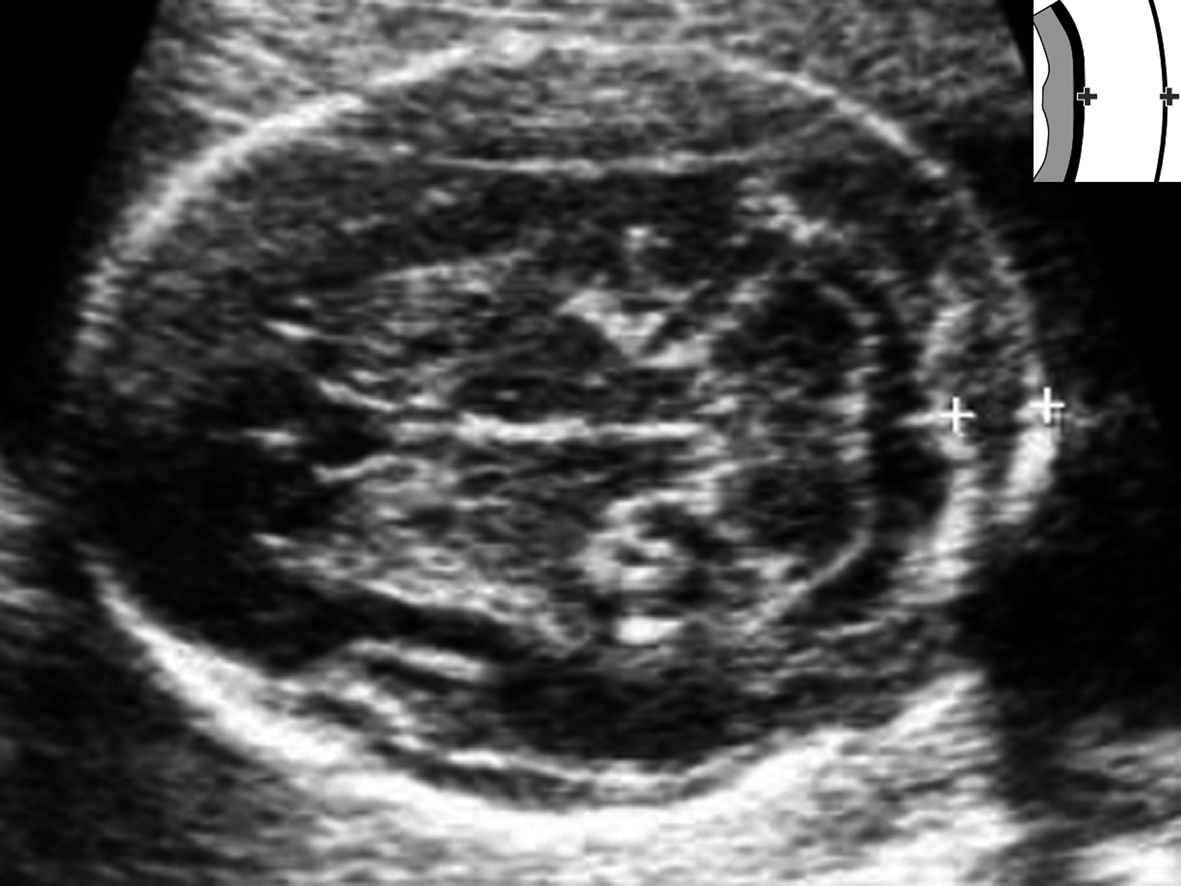

水囊状淋巴管瘤系来自淋巴系统的囊性包块,以颈部两侧及后外侧多见,显示为多房分隔状无回声区或无分隔的无回声区(图1)。产前超声显像检查比较容易显示颈部水囊状淋巴管瘤,其出现与染色体异常有明显的关系。有报道认为60%~70%的水囊状淋巴管瘤存在非整倍体,并且以Turner综合征 (45, X)常见,其他还见于18-三体综合征、13-三体综合征和 21-三体综合征。为观察水囊状淋巴管瘤分隔与不分隔的意义,Bronshtein等用了5年的时间观察了125例无分隔水囊状淋巴管瘤和25例多房性水囊状淋巴管瘤的胎儿,并与其染色体核型分析、形态学和组织学外观以及妊娠结局进行比较,发现早期妊娠中有98%的无分隔水囊状淋巴管瘤仅短暂显示,而多房的水囊状淋巴管瘤中仅有44%;更重要的是前者仅有5.7%的异常核型发生,后者高达72%;胎儿水肿的发生率在前者仅为1.7%,后者为40%;活产率在前者是94%,后者是12%。与颈部比较,在非典型部位发生的水囊状淋巴管瘤其患非整倍染色体的危险性较低。类似的结论也被以后的研究证实。

图1 胎儿颈部水囊状淋巴管瘤